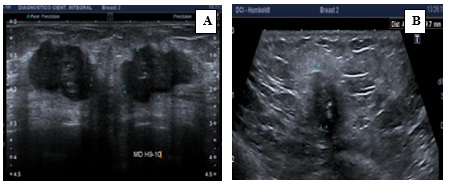

Características ecográficas del CMTN

Los resultados de las características ecográficas revelan los siguientes hallazgos en la investigación. Se describe la forma del nódulo de la siguiente manera: en su mayoría es ovalado (n = 13,76%), con márgenes microlobulados (n = 7, lo que corresponde al 41%), seguido de márgenes circunscritos (n = 5, equivalente al 29%). Además, se observa que son hipoecoicos (n = 16, lo que corresponde al 94,2%) y se ubican de manera paralela al eje cutáneo (n = 15, equivalente al 88,2%).

En relación con los hallazgos acústicos posteriores, se destaca que 14 pacientes, que conforman el 82% del grupo, no presentaban hallazgos acústicos ni calcificaciones intra ni extra nodulares.

En cuanto a la vascularización, se observa que en 14 pacientes (equivalente al 82%) no se detectó vascularización en el estudio realizado con Power Doppler. En contraste, 3 pacientes presentaban vascularización periférica, representando el 17,6% de la muestra. En ninguno de los casos se informó distorsión arquitectural ni cambios cutáneos. Sin embargo, en 15 pacientes se observaron adenopatías axilares, lo que corresponde al 88,2% del grupo estudiado.

Los hallazgos radiológicos, tanto en mamografía como en ecografía, describen características comunes de los nódulos en pacientes con CMTN, incluyendo la forma ovalada, los márgenes circunscritos o lobulados, la hipoecogenicidad y la ausencia de hallazgos acústicos posteriores. Estos resultados subrayan la importancia de la evaluación exhaustiva de las características mamográficas y ecográficas en el diagnóstico y la estratificación de los CMTN, que presentan concordancia con lo descrito en la bibliografía médica actual revisada.

Anexo 2. Imágenes ecográficas del CMTN